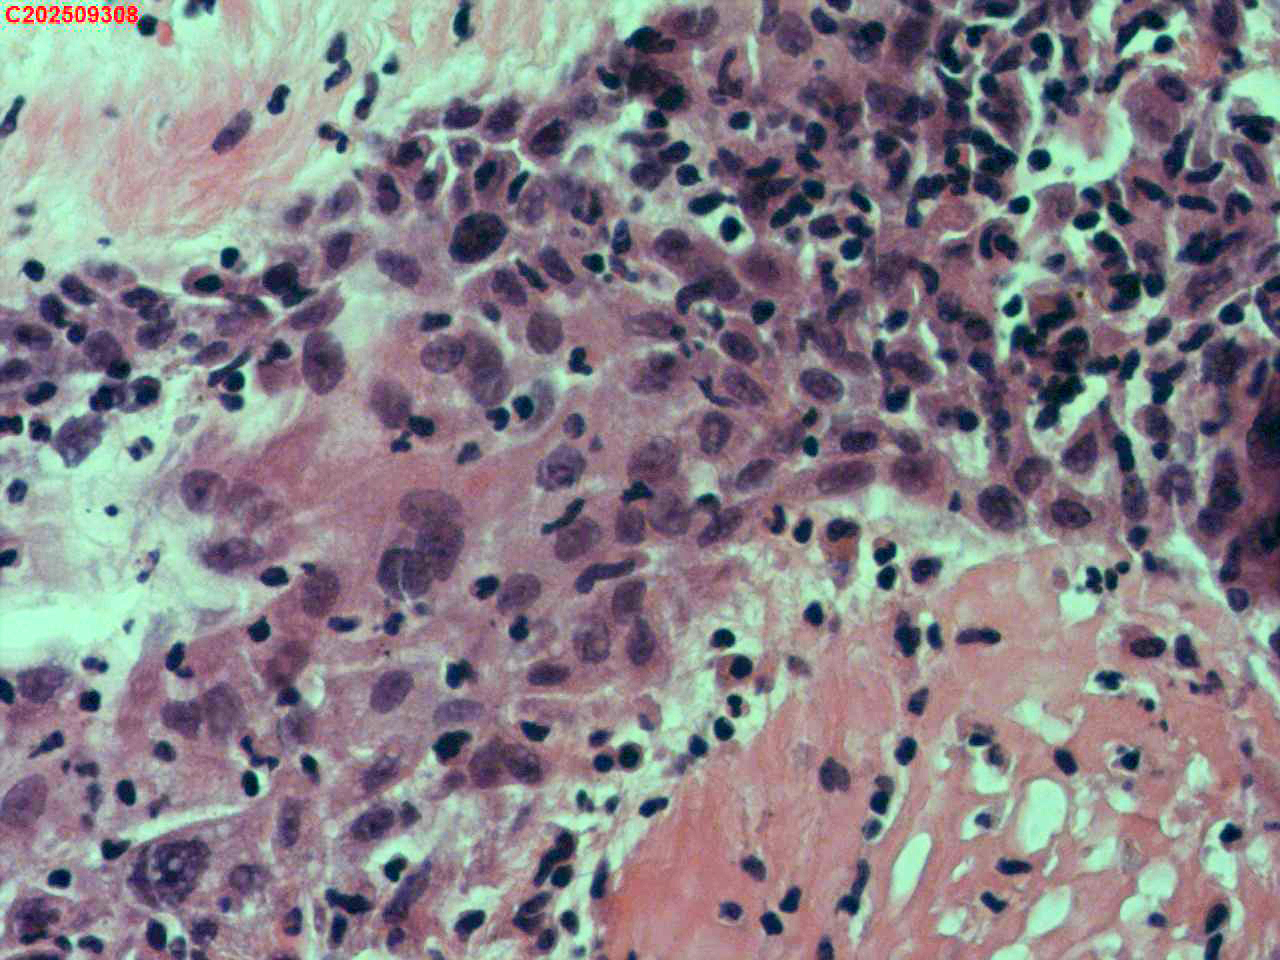

肺结核、气管结核?

胸部CT:左肺多发病变及空洞考虑结核,请结合其他相关检查。右肺上叶小点状钙化灶。左肺门增大。

纤支镜咬检

纤支镜:肉芽增生

送检粘膜鳞状上皮增生伴炎性渗出物及坏死物,建议做抗酸染色排除结核